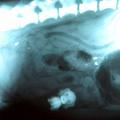

Magazin Nenavadni rentgentski posnetki Tokrat vam v galeriji na ogled ponujam nenavadne rentgentske posnetke. Oglejte si, katere nenavadne predmete so pogoltn…